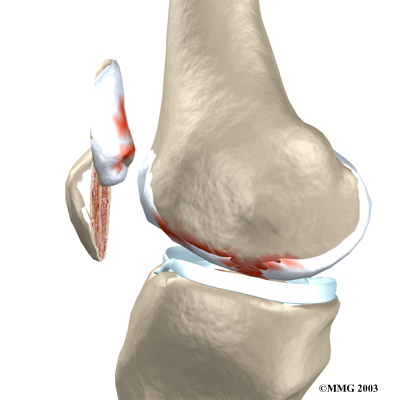

The metal femoral component is then placed on the femur. In the uncemented prosthesis, the metal piece is held snugly onto the femur because the femur is tapered to accurately match the shape of the prosthesis. The metal component is pushed onto the end of the femur and held in place by friction. In the cemented variety, an epoxy cement is used to attach the metal prosthesis to the bone.

Metal Femoral Component

The surgeon then sizes the patellar component andd puts it into place behind the patella. This piece is usually cemented in place.

Patellar Component

View animation of the completed artificial knee: